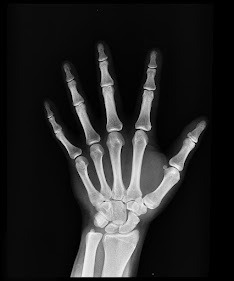

Para comenzar diremos que el cuerpo esta constituido por materiales sumamente resistentes llamados huesos. En total 206 huesos y los bebés suelen tener más huesos, pero durante el crecimiento se fusionan. El conjunto de huesos y cartílagos forman el esqueleto. Gracias a ellos podemos movernos ya que si no los tuviéramos el músculo no tendría a que adherirse para moverse.

Los huesos del esqueleto están formados por células y una matriz orgánica calcificada que proporcionan soporte para los tejidos blandos. Junto a los músculos actúan como palancas para permitir el movimiento de las diferentes partes del cuerpo. Las funciones de los huesos son:

Tipos de huesos:

Largos (ej: la tibia, el radio, el peroné, el fémur...). Constan de un cuerpo central y dos extremos. Actúan como palancas del movimiento.

Cortos (ej: las huesos del carpo y tarso). Son de pequeño tamaño y forma diversa. Su función es la de transmitir la fuerza.

Planos (ej: el cráneo, las costillas, escápula, omóplato...). Son de formas y dimensiones diversas. Protegen órganos o sirven para la inserción muscular.

Irregulares (ej: las vértebras). No presentan forma predominante. Sus funciones son variables aunque la más importante es la protección del sistema nervioso central.

Los huesos están formados por una sustancia blanda (osteína) y por una sustancia dura (sales minerales de calcio y fósforo). Constituyen un importante depósito de minerales, que son esenciales para el desarrollo del organismo y ciertos procesos metabólicos. El organismo toma el fósforo y el calcio que necesita de los fluidos extracelulares almacenados en los huesos, de forma que el esqueleto actúa como depósito y como regulador.